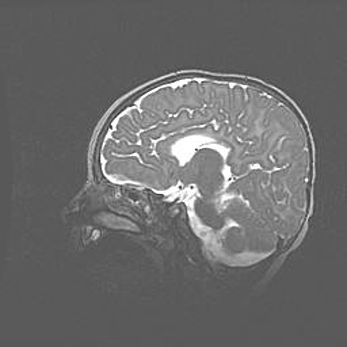

Лейкомаляция с кистозно-глиозной дегенерацией головного мозга.

Возраст: 2 месяца 25 дней

Вес: 6400 г

Окружность головы: 40 см

Срок гестации: 41 неделя

Лейкомаляцию относят к ишемически-гипоксическим повреждениям головного мозга, диагностируемым у новорожденных. При лейкомаляции в головном мозге обнаруживают очаги некроза, возникшие после тяжелой гипоксии и нарушения кровотока. В процессе морфогенеза очаги проходят три стадии: 1) развития некроза, 2) резорбции и 3) формирования глиозного рубца или кисты. Перивентрикулярная лейкомаляция (ПЛ) встречается примерно в 12% случаев среди новорожденных, обычно – у недоношенных детей, причем, частота ее зависит от массы, с которой младенец появился на свет. Наибольшее число малышей страдает лейкомаляцией, если масса при рождении 1500-2500 г.